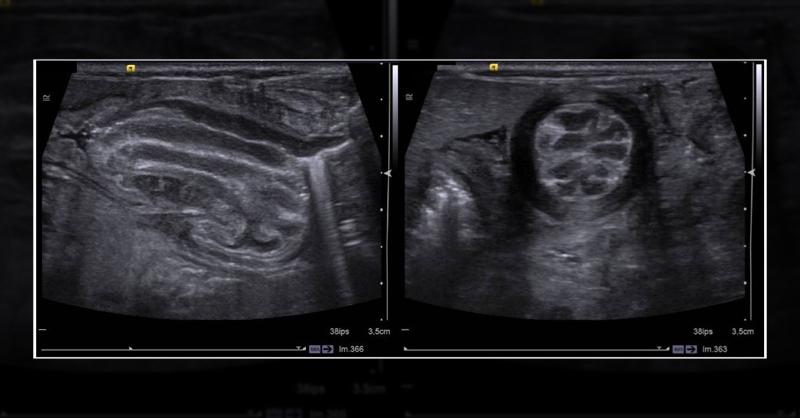

A male newborn baby, the fifth child of a couple who are first cousins, delivered prematurely at 31 weeks gestation. At birth, the infant weighed 950 g (<<−3 SD) and measured 43 cm (−1 SD), displaying severe intrauterine growth retardation. Physical examination revealed marked emaciation, absence of subcutaneous fat, muscular hypotrophy, and distin